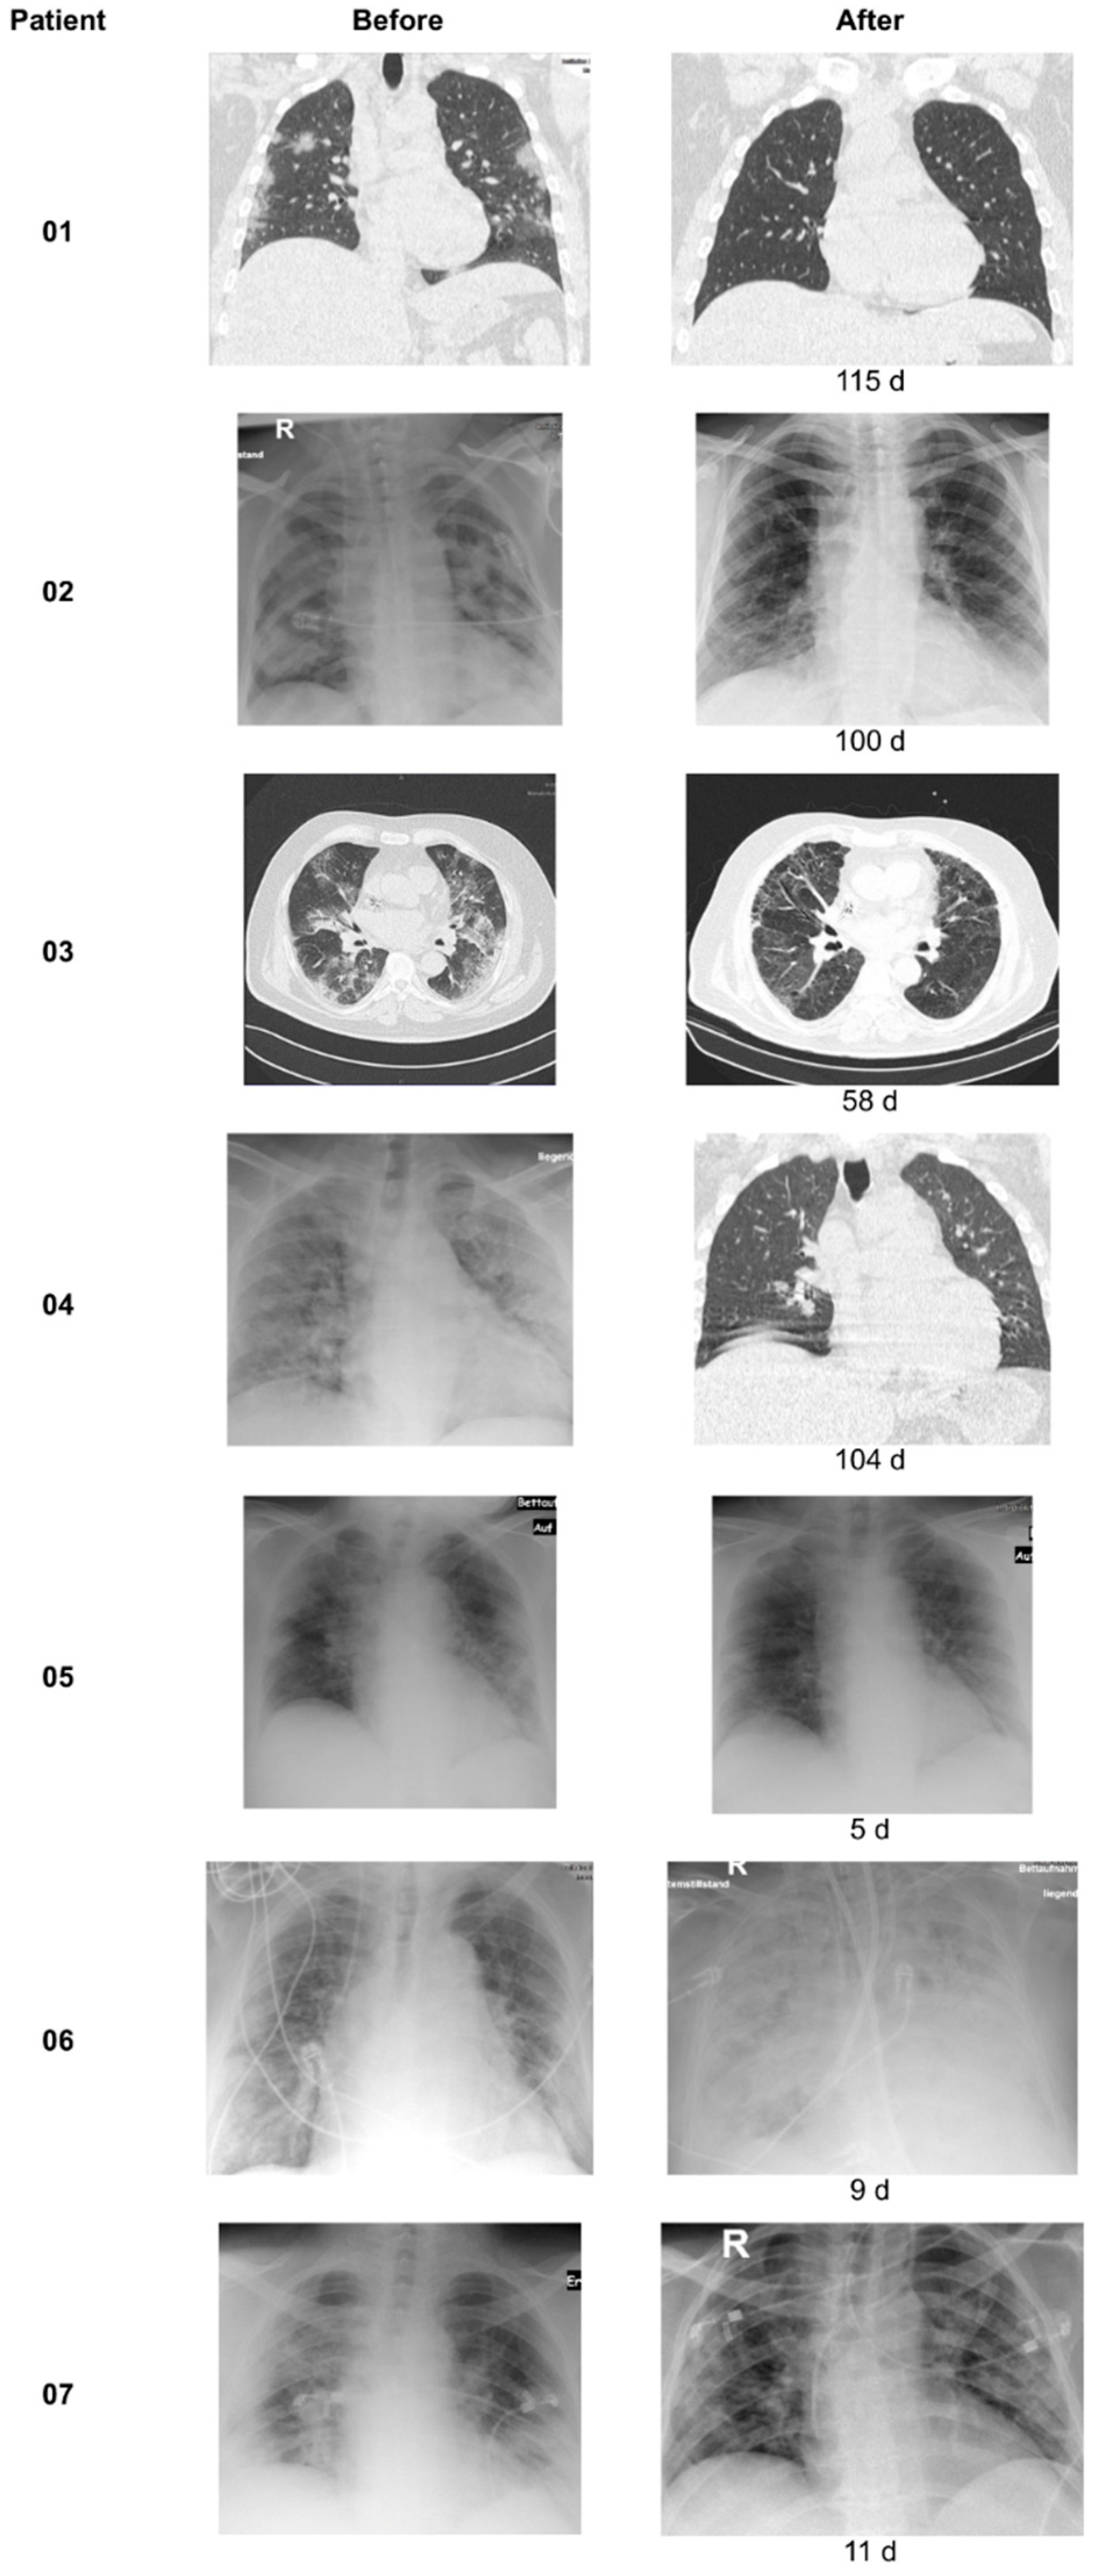

3.3. X-ray/CT Chest Scans

| Patient Number | Age | Sex | Hospitalized (Days) | Type of Ventilation (Days) | Treatment | CRP Apheresis (n) | CRP Depletion | Processed Plasma Volume | X-ray Improvement after Apheresis | Survival | Preexisting Diseases | Adipositas | Diabetes (Type) | Cardiovascular | Other | Concurrent Diseases |

|---|---|---|---|---|---|---|---|---|---|---|---|---|---|---|---|---|

| 1 | 33 | F | 7 | Nasal cannula (3) | Dex, Col, ABs | 2 | 58–67% | 7.5 L | y | y | y | n | y | Factor V Leiden, Factor II Mutation, microcytic anemia | Bacterial s.infection | |

| 2 | 54 | F | 44 | HF and NIV (24) ECMO (19) | ABs | 2 | 69–70% | 7.5–8 L | y (1st) | y | y | Type 2 | y | Bacterial s.infection | ||

| 3 | 69 | M | 75 | HF (3) M ventilation (72) | ABs | 12 | 13–84% | 6.5–10 L | y (6th) | y | y | Type 2 | y | Bacterial s.infection | ||

| 4 | 47 | M | 39 (34 HVL) | HF (1) M ventilation (24) | ABs | 7 | 20–69% | 5–10 L | y (2nd) | y | y | n | y | Bacterial s.infection | ||

| 5 | 72 | F | 9 | Nasal cannula (8) | Dex, Col | 2 | 71–72% | 4–6 L | y (2nd) | y | y | n | n | Alcohol abusement | ||

| 6 | 77 | M | 13 | HF and NIV (7) M Ventilation (5) ECMO (8) | ABs | 7 | 18–71% | 7–9 L | y (5th) Then worse until death | n | n | Type 2 | y | multimorbid | Bacterial s.infection, AKI | |

| 7 | 53 | F | 17 | Nasal cannula (7) HF (10) ECMO (10) | Dex, Col, ABs | 5 | 15–71% | 6–8.5 L | y (5th) | y | n | n | y | Viral hepatitis, Bacterial s.infection | ||